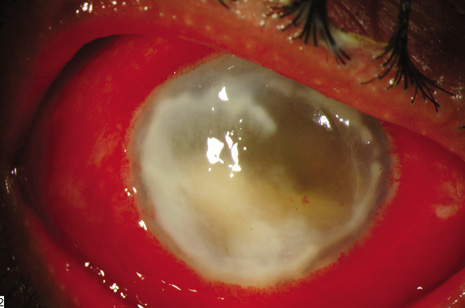

Two adverse events during or after endophthalmitis treatment may markedly influence visual acuity outcomes. Antibiotic toxicity and retinal detachment are significant because further visual loss may occur in spite of successful treatment of the infections. Macular infarction after the use of intraocular aminoglycosides (Fig. 5) is a clinically recognized complication manifesting as a relatively well-defined area of retinal whitening, often in the macula.76,77 Reported cases of macular infarction secondary to administration of intraocular aminoglycosides have been observed after excessive intraocular doses; other cases were reported after apparent injection of a recommended safe dose. A localized increase in the drug concentration in dependent areas of the retina may play a role in aminoglycoside toxicity. If some of the perifoveal capillaries are spared, retention of some central vision is possible.

Fig. 5. Macular infarction following intravitreal amikacin 0.4 mg injection. Left: The color photograph shows whitening of the retinal tissue that involves the macula as well as scattered intraretinal hemorrhages. Right: The angiogram shows prominent capillary nonperfusion that involves the macula. The organism cultured from the vitreous was Staphylococcus epidermidis. Despite resolution of the infection, visual acuity was limited to hand motion only because of the macular infarction.